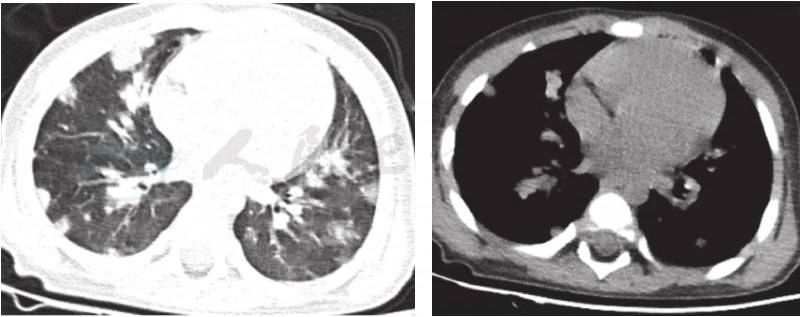

7.胸部CT(图1) ①双肺支气管肺炎待除外;②双侧胸腔积液,右侧较多;③双腋下淋巴结肿大。入院后患儿稽留高热,最高41℃,口服退热药不能降至正常,皮疹迅速加重,波及全身,呈暗红色,瘙痒明显,皮疹融合成大片,同时伴有水肿,皮肤变厚、变韧。颜面红肿明显,眼睑水肿,没有分泌物,因眼睑水肿明显,球结膜无法检查,口唇干裂,杨梅舌阳性明显。手足均明显充血肿胀。颈部淋巴结肿大。请感染科会诊除外传染性疾病;皮肤科会诊:考虑多形红斑?各种感染、药物及内脏疾病等原因均可导致本病。避免可疑致敏因素,给予脱敏治疗,加用氯雷他定、盐酸左西替利嗪片口服,白色搽剂适量外用,阿奇霉素抗感染治疗。

图1 入院时完善肺CT

提示:双肺支气管肺炎待除外;双侧胸腔积液,右侧较多;双腋下淋巴结肿大